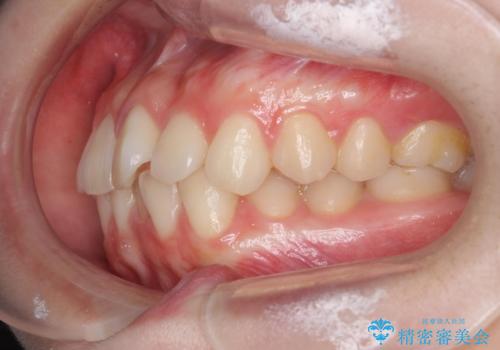

前歯のねじれをマウスピース矯正で治したい

- 前歯のねじれや がたつきを治したい、マウスピース矯正治療を希望され来院されました。

初診時程度のがたつきやねじれであれば、26枚以下のマウスピース矯正 モデレートプランで、比較的リーズナブルに矯正治療を受けていただくことができます。

実際の治療期間は約半年で仕上がりのような綺麗な歯並びを手に入れることができました。